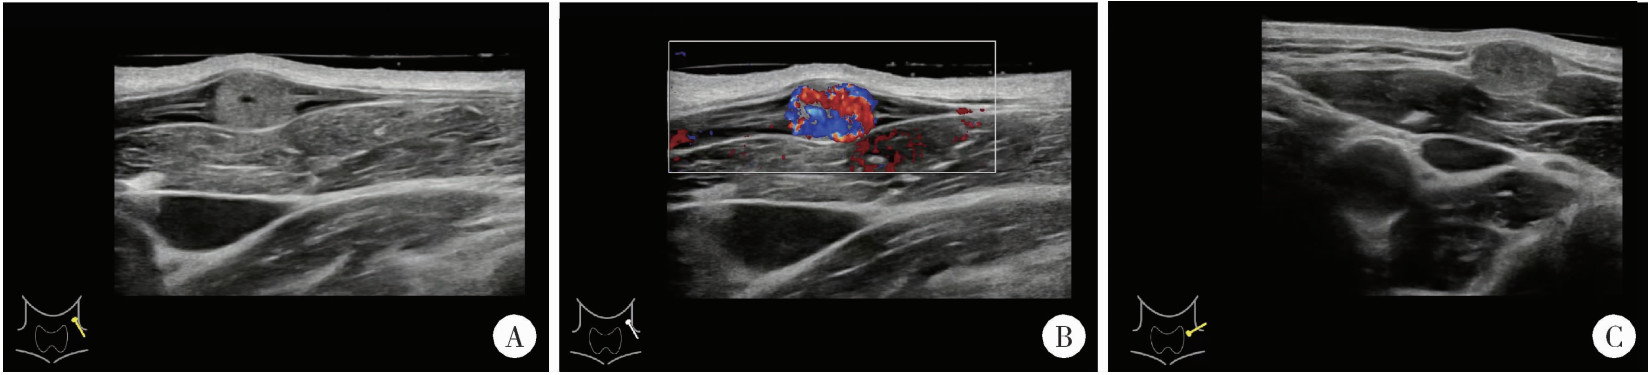

患者于术后第2日出院,出院时切口对合良好,未见明显红肿、渗出,颈部运动不受限。术后病理回报证实IPEH诊断:肉眼可见血管内灰白结节样物一枚,最大径0.6 cm;镜下可见血管内乳头状内皮增生,其内可见血管再通,血管壁纤维组织增生明显(图 3)。患者术后2周复诊可见一长度1.5 cm手术瘢痕,愈合情况尚可,稍红肿,无痛,未见渗出、渗血,颈部各方位运动自如。

图3 IPEH的病理特点

Figure 3 Pathological microscopic features of IPEH

A, full view of intravascular tumor (20×); B, vascular endothelial hyperplasia, fibrous tissue hyperplasia, fibrous interstitial hyperplasia and recanalized vessels (40×); C, papillary structure (200×); D, endothelial lining fissures and papillary hyperplasia (200×); E, no obvious polymorphism of endothelial cells (400×); F, papillary structure (400×).IPEH, intravascular papillary endothelial hyperplasia.